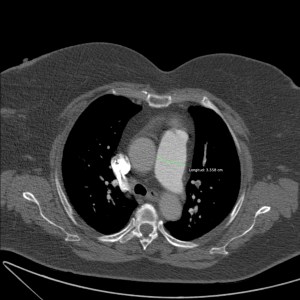

Relación VI/VD > 1. Signo de muy mal pronóstico.

Relación VI/VD > 1. El tabique interventricular está empezando a desviarse hacia el VI. Signos de muy mal pronóstico.